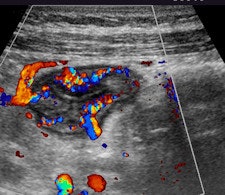

Contrast-enhanced ultrasound (CEUS) is the most sensitive method for detecting even minor blood flow in the bowel, which is a relevant sign for inflammatory bowel disease (IBD). In terms of resolution, CEUS is a more powerful tool than ultrasound alone for characterization of inflammatory masses.

This is the view of Dr. Stephanie Wilson, a clinical professor of radiology at the University of Calgary in Canada. The use of contrast agents in detecting IBD can make a very positive contribution to patient management when the activity of the disease is uncertain in an identified loop of thickened bowel, as may be the case when the loop is deep in the abdomen or the signals of blood flow -- shown by Doppler sonography -- are too weak, she noted.

"Contrast agents are also beneficial in the resolution of an inflammatory mass as is frequently shown on imaging studies of those with IBD. While the grayscale features of abscess and phlegmon may be specific, there are many instances when this distinction cannot be made with conventional ultrasound alone. The injection of a microbubble contrast agent will show diffuse enhancement of an inflammatory phlegmonous mass, whereas an abscess will be avascular in the regions where there is pus," said Wilson, who will present on this topic during the opening day of the World Federation for Ultrasound in Medicine and Biology (WFUMB) congress, to be held in Vienna from 26 to 29 August.